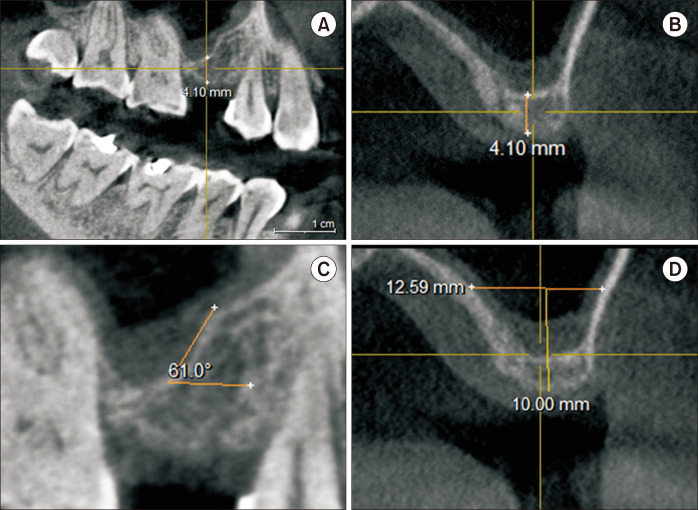

Transcrestal sinus floor elevation (tSFE) is a useful method for vertical bone augmentation in the posterior maxilla at the time of implant placement. However, this is a blind surgical technique with a risk of perforating the Schneiderian membrane. In this article, we present a simple technique to perform tSFEs using ridge spreaders. With this technique, the tSFE is performed in a slow and controlled manner without the entry of instruments into the maxillary sinus. Furthermore, many clinicians may find they already have the necessary surgical tools within their armamentarium. This precludes the need for rotary drills that spin at high revolutions per minute in the sinus cavity or osteotomes which may result in an uncomfortable patient experience. In order to fully exemplify its clinical utility in performing successful tSFE without membrane perforation, we present this surgical technique in a case with limited residual bone height and a steeply oblique sinus floor.